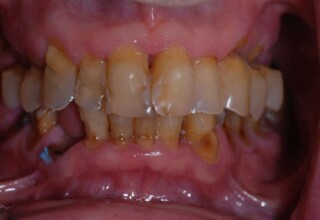

Ολική Στοματική Αποκατάσταση σε Εμφυτεύματα με διαφορετική προσέγγιση στην Άνω και Κάτω Γνάθο

Κάτω γνάθος: εξαγωγές, άμεση τοποθέτηση εμφυτευμάτων και άμεση φόρτιση(την ίδια ημέρα) με προσωρινή γέφυρα

Άνω γνάθος: σταδιακές εξαγωγές, σταδιακή τοποθέτηση εμφυτευμάτων και σταδιακή ενσωμάτωση τους στην προσωρινή γέφυρα ώστε η ασθενής να μην μείνει ούτε μια ημέρα χωρίς αποκατάσταση. Στόχος η συνεχής λειτουργική και αισθητική αποκατάσταση της ασθενούς χωρίς άμεση φόρτιση των εμφυτευμάτων λόγω ανατομικών ιδιαιτεροτήτων.

Χρησιμοποιήθηκαν παλαιές χαμογελαστές φωτογραφίες της ασθενούς γιατί είχε χαθεί τελείως το φυσικό σχήμα των δοντιών εξαιτίας των πολλαπλών προσθετικών προσπαθειών που είχαν γίνει στο παρελθόν. Μεταφέρθηκε στην προσωρινή γέφυρα η σχέση των φυσικών δοντιών μεταξύ τους άλλα και με τα χείλη. Δοκιμάστηκε η φώνηση και η μάσηση με δυο διαφορετικές προσωρινές άνω γέφυρες και εκτιμήθηκε η αισθητική απόδοση τους. Αφού επιτεύχθηκαν σε βαθμό ικανοποιητικό η φώνηση και η αισθητική εμφάνιση της οδοντοφυΐας, η προσωρινή αποκατάσταση χρησιμοποιήθηκε ως οδηγός για την τελική.

Αρχικό

Ενδιάμεσο

Τελικό